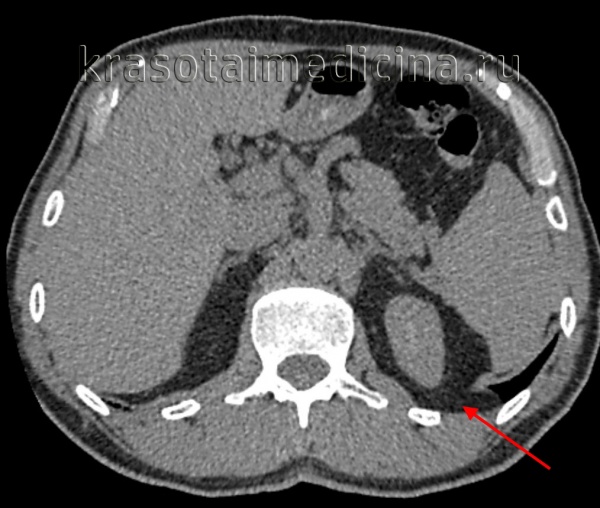

КТ органов брюшной полости. Грыжа пищеводного отверстия диафрагмы. Пролабирование перигастральной клетчатки в грудную полость через расширенное пищеводное отверстие